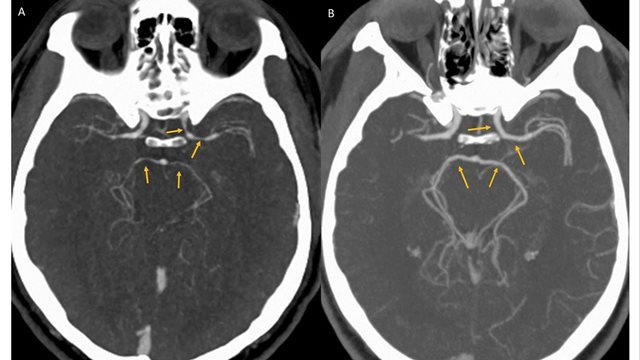

「世界一辛い」トウガラシを食べた男性の脳血管に狭窄が見つかった

(CNN) 米ニューヨークで開かれたトウガラシの大食い大会で、世界一辛いといわれる「キャロライナ・リーパー」というトウガラシを食べた挑戦者の男性が、直後に激しい頭痛を訴えて病院に運ばれた。神経科の専門医が9日の医学誌BMJに発表した症例報告で明らかにした。

患者は34歳の男性で、頭と首の激しい痛みを訴えて病院の集中治療室に運ばれた。大会でキャロライナ・リーパーを食べた直後に後頭部に激痛が走り、頸部から頭部にかけてたちまち痛みが広がったという。

病院で検査した結果、脳出血や脳梗塞は起きていないことが判明。しかしCT血管造影を使って脳内の血管を調べたところ、左側の内頸(ないけい)動脈など脳につながる4本の血管に大きな狭窄(きょうさく)が見つかり、トウガラシが原因と思われる可逆性脳血管攣縮(れんしゅく)症候群(RCVS)と診断された。

専門家によると、RCVSは雷に打たれたような激しい頭痛を伴う疾患で、大抵は数日から数週間で回復するが、重症化すると命にかかわることもある(略)

男性は治療を受けて快方へ向かい、数日後に退院した。5週間後の検査では、血管狭窄の症状は解消されていたという。